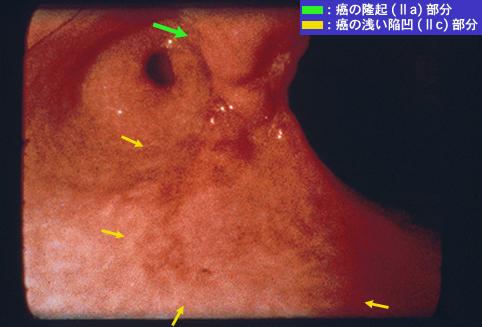

clasificación del pacienteTumor Epitelial Maligno/Cáncer a células en Sello de Anillo

parte(separada por órganos)estómago(región)/ángulo

método de exámenEndoscopia

clasificación ectoscópica de tumoresTipo 0(tipo superficial)/Tipo IIc(IIc+IIa)

diámetro mayor del tumor40 -

grado de penetraciónsm